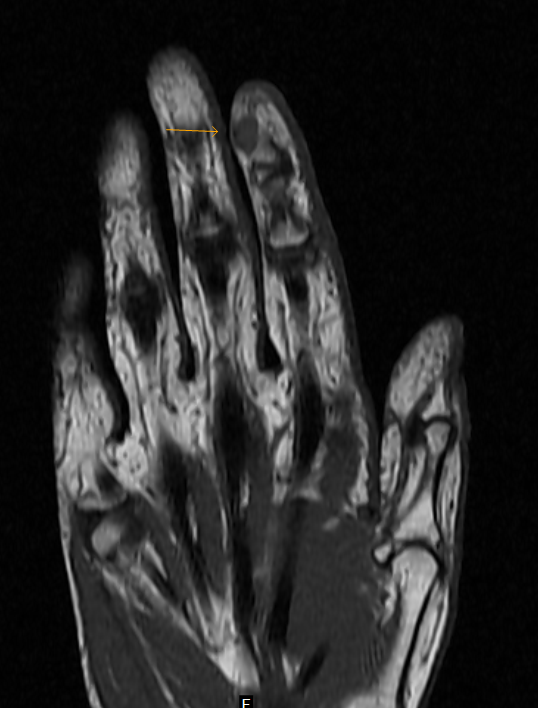

Гломус ангиома: Макропрепарат под микроскопом